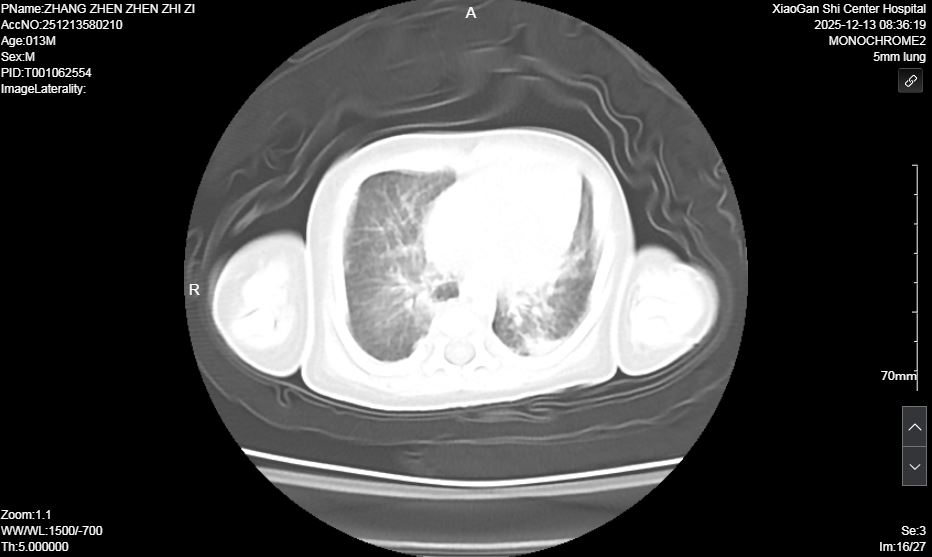

術前肺部超聲及CT均提示雙肺實變明顯

患兒入院后,NICU團隊立即啟動危重新生兒搶救預案。經快速檢查,初步診斷為宮內感染所致的足月兒急性呼吸窘迫綜合征(ARDS),該疾病極易合并肺高壓、氣胸、肺出血、呼吸衰竭等嚴重并發(fā)癥,屬于新生兒急危重癥,救治難度極大。團隊立即按新生兒ARDS診療規(guī)范進行氣管內給予肺表面活性物質,循環(huán)支持,抗感染、持續(xù)機械通氣、營養(yǎng)支持等對癥治療。然而,由于原發(fā)疾病嚴重,患兒經歷7天機械通氣后,病情出現反復,肺部影像學顯示雙肺實變明顯,脫氧撤機困難。